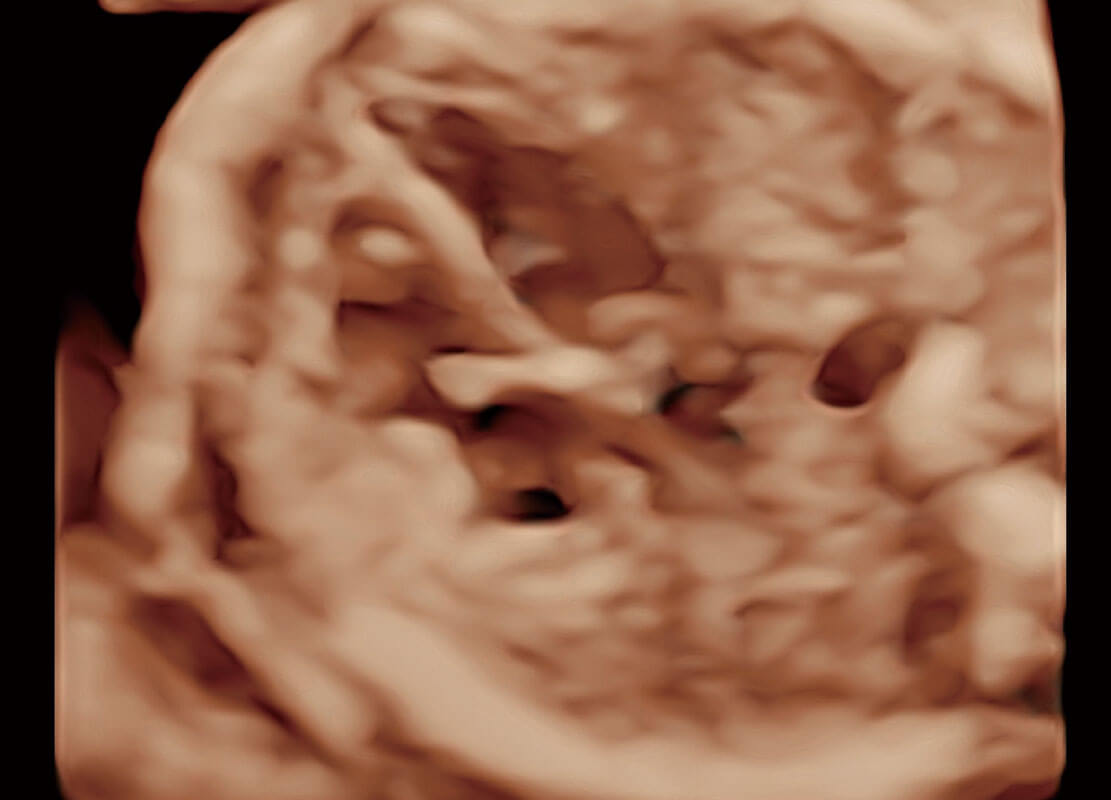

P60搭载一系列胎儿心脏成像技术,实现精细的胎儿心脏评估。

右室双出口

胎心容积成像